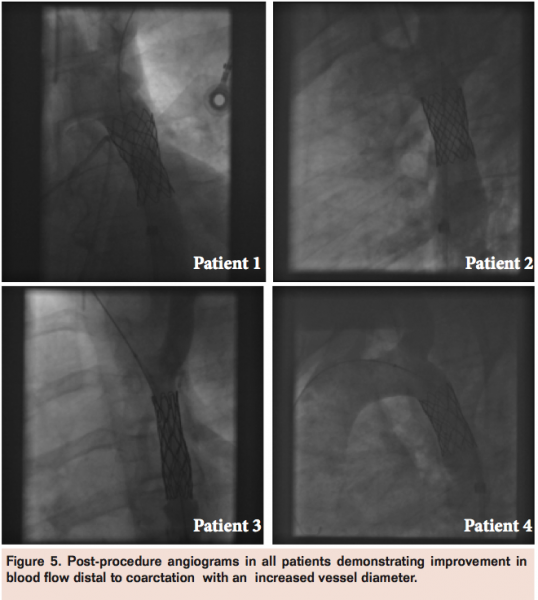

A 38-year-old man presented with symptoms of dyspnea on exertion, orthopnea, and paroxysmal nocturnal dyspnea. An echocardiogram showed a bicuspid aortic valve, mild mixed aortic valve disease, and a dilated left ventricle with mildly impaired systolic function. Cardiac MRI revealed severe coarctation of the aorta with a peak gradient of 50 mm Hg and diastolic continuation of flow across the stenotic area. While awaiting definitive management, he presented with infective endocarditis affecting his aortic valve. He was transferred to our tertiary unit with evidence of worsened aortic regurgitation. He was treated with appropriate antibiotics and definitive treatment was carried out in a hybrid manner with initial stent angioplasty of the coarctation followed by surgical aortic valve replacement while under the same general anesthetic. At cardiac catheterization, vascular access was obtained via the right femoral artery using a 6 Fr sheath. Aortography demonstrated a long segment of stenosis distal to a focal area of severe narrowing (Figure 1). There was a peak-to-peak pullback gradient of 36 mm Hg across the stenosis. The aorta measured 17 mm proximally and 30 mm distally with a total length of 47 mm. A 34 mm covered CP stent (8 zig, NuMED, Inc.) was deployed across the focal stenosis and expanded to 20 mm with 5 atm pressure. This resulted in relief of the obstruction with only a residual 5 mm Hg pullback gradient but no visible obstruction distal to the stent.